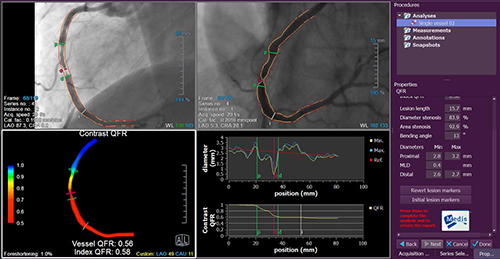

QCA,LVA解析システムとして世界中で広く採用されている「QAngio XA」, 「CAAS」をはじめ,Strain解析機能を一新した心エコー画像解析システム「TomTec-Arena」,NIRS解析に対応したIVUS画像解析システム「CAAS IntraVascular」, 「QIvus」,心臓MR画像による肉柱を含む心筋と心内腔を自動で区別するMassK Mode機能が新たに追加された「Medis Suite MR」,近年その重要性が見直されつつある冠動脈疾患の機能的虚血評価をアンギオ画像のみで簡便に行えることで注目を集めるQFR(Quantitative Flow Ratio)解析を搭載した「QAngio XA 3D」など,臨床現場に限らず研究や教育にも活用頂ける豊富なラインナップを揃えてお待ちしております。是非この機会に実機に触れてみて下さい。

※QAngio XA 3Dは学術研究用プログラムです。臨床診断の目的では使用出来ません。

QAngio XA 3D(QFR解析)